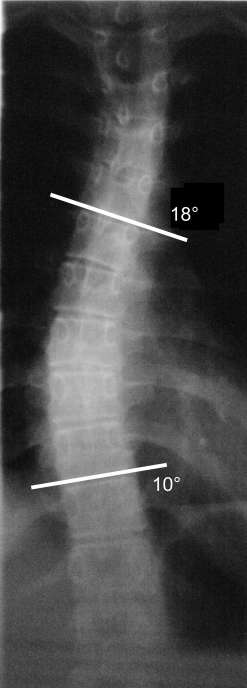

Anschließend habe ich die beiden Winkel oben und unten mit GIMP ausgemessen, das geht wirklich sehr schnell und einfach (Ergebnis siehe Anlage). Der COBB-Winkel von 28° ergibt sich als Summe der beiden Einzelwinkel. Diese Info (COBB-Winkel) hat der Orthopäde, der das Bild aufgenommen hat, uns nicht gegeben.

- Röntgenbild mit eingezeichneten Winkeln

die Winkel kann man mit GIMP messen, wie von BZebra im ersten Beitrag auf Seite beschrieben. Wenn man das digitale Bild in GIMP geöffnet hat, wählt man die Funktion "Abstände und Winkel messen". Dann zeichnet man mit der Maus (linke Maustaste gedrückt halten) eine gerade Linie in das Bild, wie z. B. die beiden weißen Linien in unserem Röntgenbild. Im GIMP-Fenster unten wird dann von der Software der Winkel angezeigt zwischen der Linie und der Waagerechten.